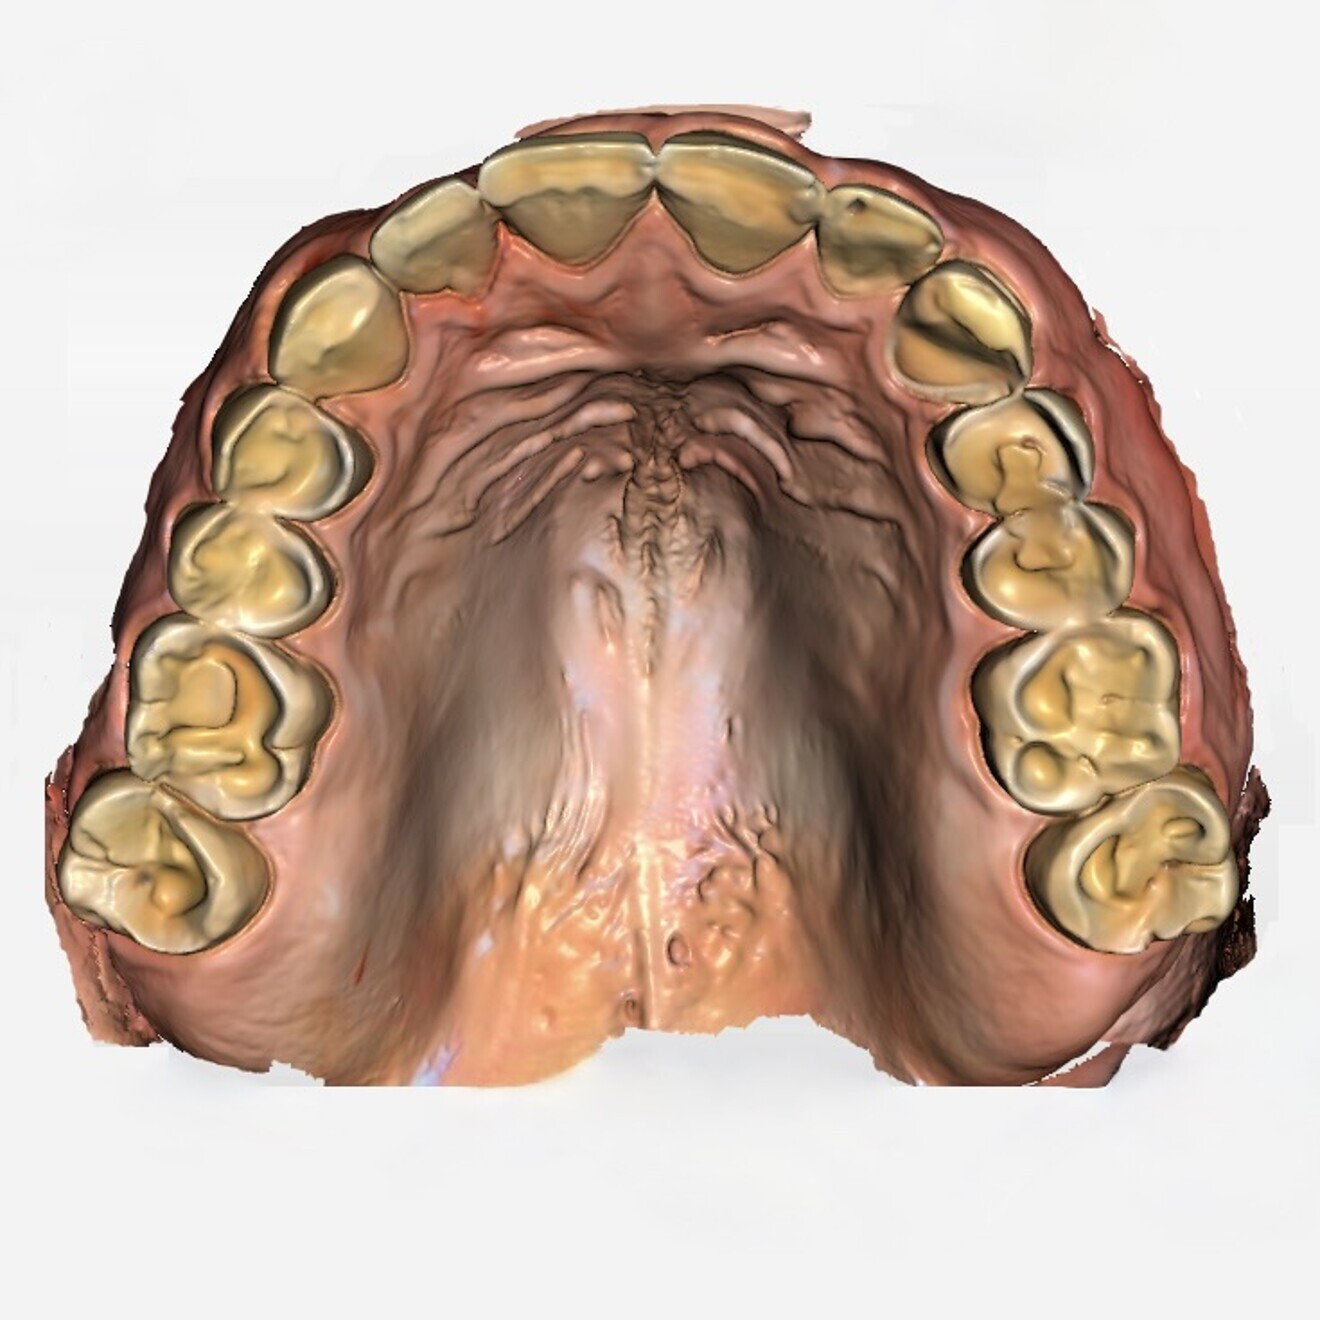

Fig. 3a: Digital scan of the initial situation. Upper jaw.

To treat this case, the conventional approach of adapting the masticatory system to a new maxillomandibular relationship with increased OVD using a mandibular splint was chosen. For the manufacture of the splint, an intra-oral scan (Primescan, CEREC Software 5.2.9, Dentsply Sirona) was performed (Figs. 3a & b). The maxillomandibular relationship in centric occlusion was digitally registered by means of an anterior jig and a facial scan. The scan data was sent to the dental laboratory, and the models were aligned in a virtual articulator using exocad DentalCAD. The required OVD was determined by means of a digital diagnostic wax-up. The splint was digitally designed in the lower jaw and fabricated from polymethylmethacrylate (PMMA) using the subtractive technique (Figs. 4a & b).

The scan data of the upper and lower jaw was digitally matched with the digital scan of the initial situation by means of anatomical reference points in the exocad software. The maxillomandibular relationship initially determined for the fabrication of the splint could thus be adopted, and the digital design of the restorations could be carried out. For stability, the provisional restorations in the anterior and posterior regions were designed as contiguous segments in this case. The STL data set of the restorations was then transferred to the CAM software Netfabb 2022.0 (Autodesk), and supporting structures were added to the non-functional areas (Fig. 8). The long-term provisional restorations were printed from V-Print c&b temp (Fig. 9).